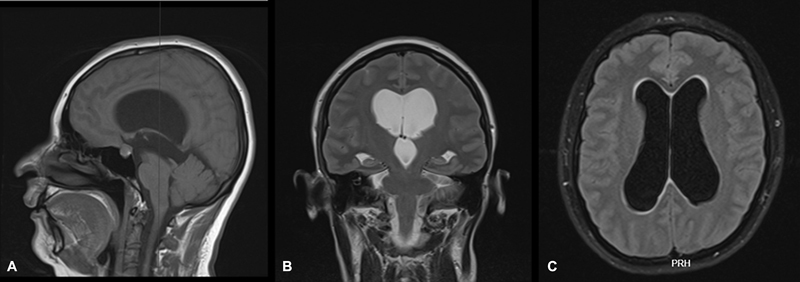

Introduction  Hydrocephalus is a condition characterized by the abnormal accumulation of cerebrospinal fluid within the brain's ventricular system. It can stem from obstructive and nonobstructive causes. Pregnancy introduces physiopathological changes that may heighten the risk of developing or worsening symptomatic hydrocephalus. Nevertheless, comprehensive reports on this aspect, especially regarding surgical interventions, remain scarce. Case Report  A young woman with a history of recurrent headaches experienced a worsening of her symptoms at the onset of her pregnancy. A magnetic resonance imaging (MRI) in the first trimester revealed increased ventricular dilation, indicating an obstructive cause due to aqueduct stenosis. During a neurosurgical board meeting, treatment options were discussed, considering the identifiable obstruction, the heightened intra-abdominal pressure associated with pregnancy, and the risk of ventricular shunt dysfunction. The patient underwent an endoscopic third ventriculostomy (ETV) without complications, leading to both symptom relief and a successful conclusion to the pregnancy. Discussion  Neurosurgical procedures in pregnant women are uncommon due to the increased risks to both the mother and the fetus. However, when performed by a qualified multidisciplinary team, they can lead to positive outcomes. In cases of hydrocephalus during pregnancy, ETV appears to be a viable alternative for surgical intervention, particularly when hydrocephalus becomes symptomatic and an obstructive cause is identified, whether in patients with existing shunts or those with newly developed hydrocephalus.

Abstract Image